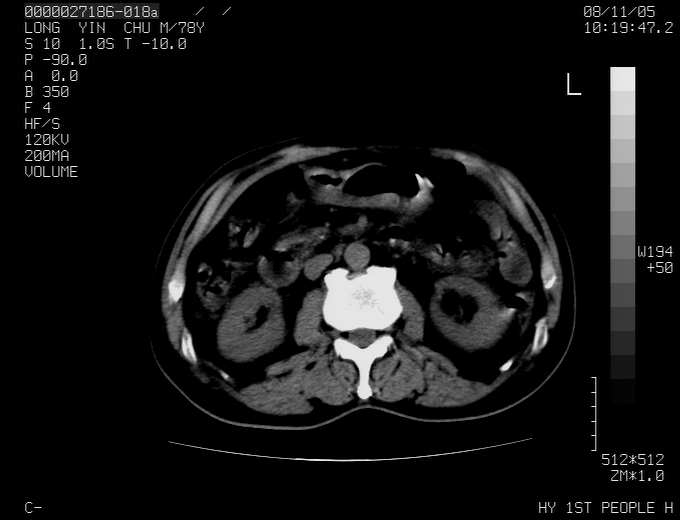

标题: CT16532:M78Y,肝脏病变,请会诊 [打印本页]

标题: CT16532:M78Y,肝脏病变,请会诊

腹胀,腹痛就诊,男性,78岁,外院b超未见异常。

肝ca,脾肾转移

考虑弥漫性肝癌并脾及双肾转移.双侧胸水.

图片质量欠佳:多考虑:左侧肾癌。脾脏转移!胸膜转移!

肝脾肾转移瘤可能性大,左肾不除外梗塞,双侧胸水

考虑弥漫性肝癌并脾及双肾转移,双侧胸水。

考虑肝癌并双肾及脾脏转移;双侧胸腔积液。